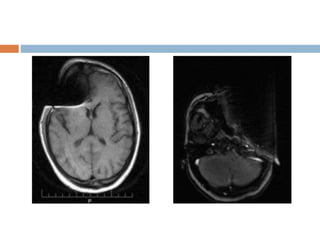

Magnetic suscepbility artifact

 Distortion in the MR image especially seen in

while imaging with metallic orthopedic hardware

or dental work.

 Magnetic field inhomogenetics introduced by the

metallic object in to homogeneous magnetic

field.

 Greater at high magnetic field strength.

 Worst with long TE and gradient echo

sequences.

 Appearance

Bright and dark areas

 Solution

Larger receiver bandwidth

Gradient echo and echo planar sequences

should be avoided.

The use of echo spin particularly fast spin

echo sequences should be considered.

Magnetic suscepbility artifact Distortion in the MR image especially seen in while imaging with metallic orthopedic hardware or dental work.  Magnetic field inhomogenetics introduced by the metallic object in to homogeneous magnetic field.  Greater at high magnetic field strength.  Worst with long TE and gradient echo sequences.

• 36.

 Appearance Bright anddark areas  Solution Larger receiver bandwidth Gradient echo and echo planar sequences should be avoided. The use of echo spin particularly fast spin echo sequences should be considered.